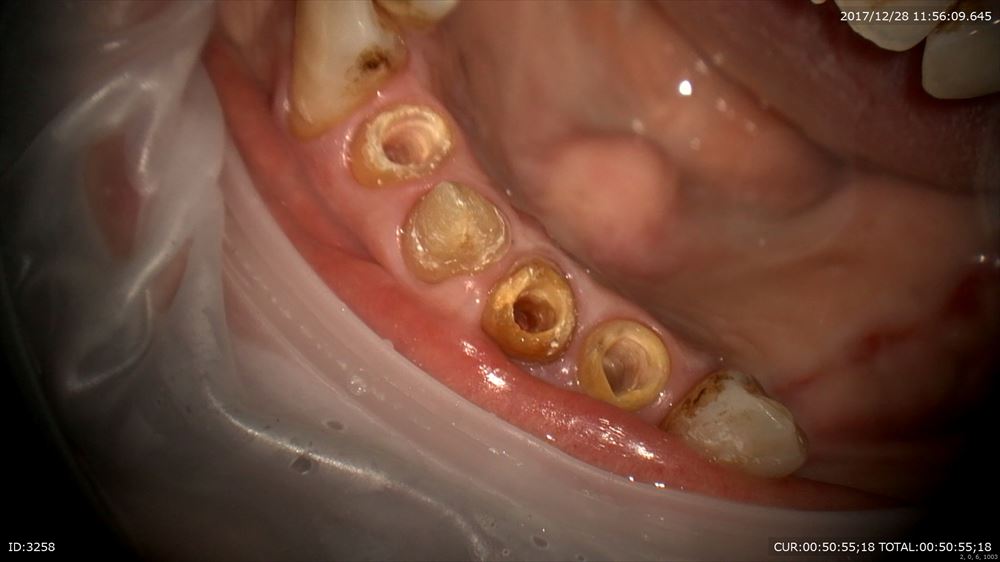

次は精密根管治療

前回から根管治療開始。1回の治療で「今まで腫れていたのが嘘みたい!!」とお褒めのお言葉を頂きました。歯は原因が取れれば治癒の方向へ向かいますとお話ししました。私も嬉しい!!根管治療は回数ではありません。当院では平均3回で終了しています。回数が増えるほど、しかも、もしその際ラバーダムなど無菌的処置をしていなければ感染する機会が増え一向に治りません。だから当院は短期集中。

綺麗になりました。

術前と術後

もちろん無痛です。